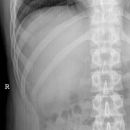

Thorax p.-a.

Streng symmetrisch, Schulterblätter außerhalb der Lunge. Atemphase: maximale Inspiration. Bei Verdacht auf Pneumothorax in maximaler Expiration die Aufnahme durchführen.

Abgebildet müssen sein: beide Lungenflügel, PC-Winkel und Lungenspitzen. Die ersten 3-5 Rippen sollten schwach erkennbar sein, die inneren Scapularänder sollten außerhalb des Thorax liegen.